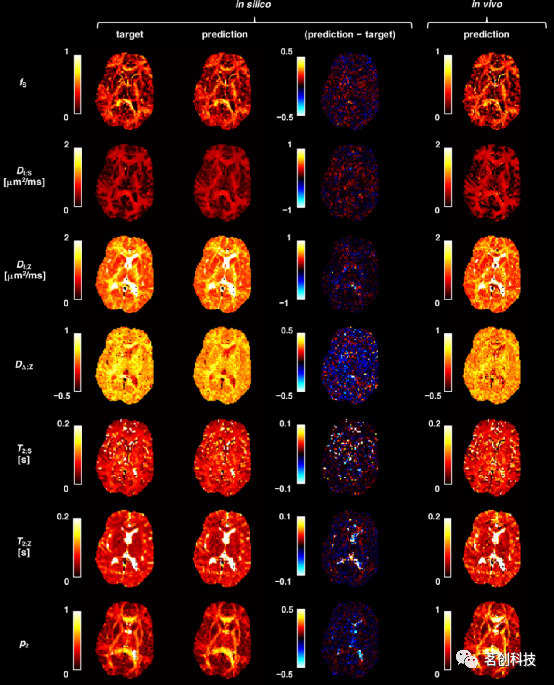

在同一台计算机上,基于SNN的参数估计比NLLS拟合的速度快约104倍,得到的参数与地面真实目标一致,并且保留了具有不同(T2,D)属性的区域之间的对比度(图1)。例如,估计的fS和p2通常在WM区域中较高,而在定向相干的WM区域(如胼胝体)中最高。然而,在T2;Z中观察到对比度降低,其中WM(较暗)和皮层GM(较亮)区域之间的区别在地面真值图中更为明显。T2;Z估计值还表现为在长T2区域(如侧脑室)中,地面真值和估计参数之间存在显著差异。估计值与地面真值之间的最大总体差异为DΔ;Z,可能是因为当|DΔ;Z|<0.5时信号对其不敏感。使用在合成数据上训练的ANN直接拟合体内实验数据,得到了噪声更大的图。然而,它保留了一种解剖学上似乎合理的对比。考虑到silico地面真值图和网络估计之间的强相关性,体内参数图的噪声可能是因为SMR模型不能准确地表示潜在的活体数据。

图1.将训练过的网络部署到未经训练的silico和活体数据上,可以在10s内提供解剖学上合理的参数图。

从深层网络估计的参数图与其各自的地面真值目标非常一致。基于DNN的拟合导致网络估计和地面真值参数目标之间的相关性略强。尽管DNN和SNN的体内图相似,但在DΔ;Z和T2;Z中可以发现差异。DNN产生DΔ;Z图噪声更大,而T2;Z图在WM和皮层GM之间具有更高的对比度。这表明DNN更容易受到SMR信号预测和体内测量数据之间差异的影响。